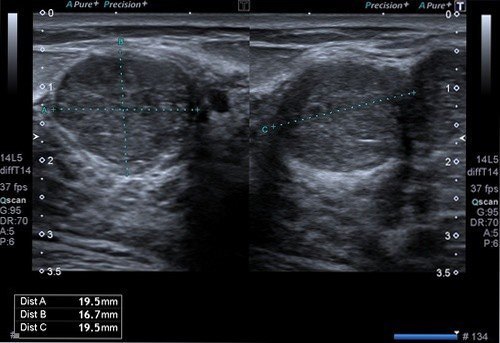

Memede saptanan kitlelerin ultrasonu özelliklerinin değerlendirilmesi ile iyi huylu, kötü huylu ya da şüpheli olduğu söylenebilir. İyi huylu kitlelerin normal meme dokusuna göre kötü huylu kitlelerle dönüşmesinin riski daha yüksek olduğu için 3 ya da 6 ay aralıklarla meme ultrasonu ile takip edilmelidir. Şüpheli kitlelerin kısa aralıkla takibi, mamografi ve meme MRG ile değerlendirilmesi gerekebilir. Meme ultrasonunda büyük olasılıkla kötü huylu olduğu düşünülen kitleler için ise meme ultrasonu eşliğinde biyopsi yapılması gerekecektir.